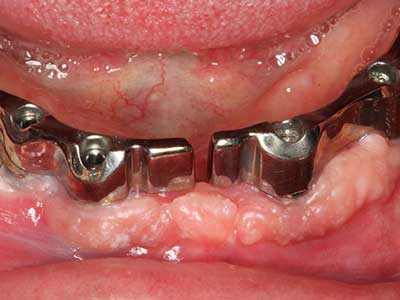

Knochengewebe ist nicht nur rein mineralisch, sondern auch in wesentlichen Anteilen aus Kollagenfasern aufgebaut. Dies gewährleistet neben einer guten Druckfestigkeit eine gewisse Flexibilität, welche für die Durchführung von Augmentationen genutzt werden kann. Bei der klassischen Expansionsplastik im Sinne eines Bone Splittings wird der atrophierte Kieferkamm in seiner Längsachse gespalten und nach Erreichen einer ausreichenden Osteotomietiefe vorsichtig aufgedehnt (Abb. 13-16), idealerweise ohne den Kiefer wesentlich zu deperiostieren (Brugnami, Caiazzo et al. 2014, Stricker, Fleiner et al. 2014). Bewährt haben sich Schrauben- und Plattensysteme mit zunehmender Expansionsdistanz, um die beiden Knochenlamellen unterhalb der Bruchschwelle voneinander zu distanzieren. In der Regel werden Restknochenbreiten von mindestens 3-4 mm gefordert (Chiapasco, Zaniboni et al. 2006), um eine ausreichende Flexibilität und knöcherne Bedeckung der einzubringenden Implantate zu gewährleisten. Ggf. kann eine ein- oder beidseitige vertikale Entlastungsosteotomie die Flexibilität verbessern. Als Alternative zur klassischen Technik wurde eine Kombination mit weiteren augmentativen Techniken vor allem auf der bukkalen Seite beschrieben.

Mittels Piezosägen erfolgt die Anlage des Splittings besonders schonend und ohne wesentliche Dimensionsverluste, so dass sich keine signifikanten Unterschiede von Implantaten im gesplitteten Kiefer im Vergleich zum nicht defizitären Alveolarkamm gezeigt haben (Chiapasco, Zaniboni et al. 2006, Danza, Guidi et al. 2009). Gerade beim lokal begrenzten und tiefen Splitting ist jedoch stets auf eine ausreichende Wasserkühlung zu achten, um thermische Belastungen in den apikalen Osteotomiebereichen zu vermeiden.